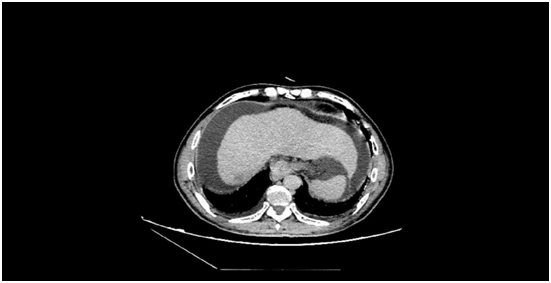

術(shù)前發(fā)現(xiàn)患者的肝臟5段有一個5.5cm大小的惡性腫瘤,此外還有大量腹水、門脈高壓癥、脾功能亢進(jìn),同時合并有消化道出血、肝功能差等癥狀。而在患者的肝臟7段,亦存在一個2cm大小的肝內(nèi)轉(zhuǎn)移灶。

術(shù)后復(fù)查CT見腫瘤全部失去了活性